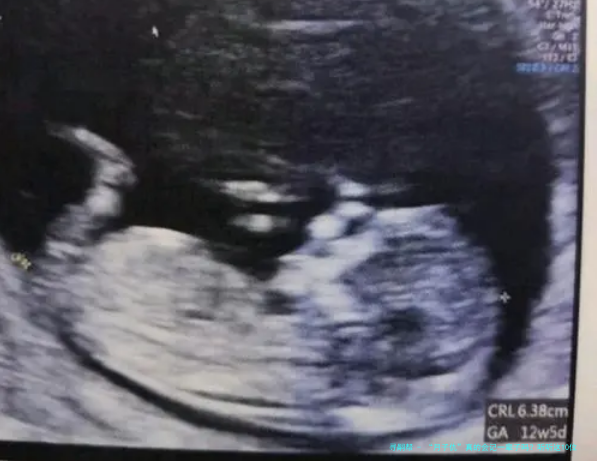

Tips: 每个家庭的生育情况都是独特的,没有一刀切的方案。全民健康建议您在了解基础知识后,结合自身的年龄、身体状况和经济条件,与医生深入沟通。全民健康的专业顾问随时可以帮您分析和解读医生的建议。